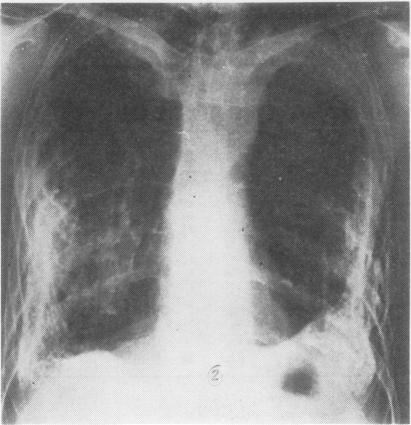

透闪石粉尘导致的胸膜钙化、胸膜间皮瘤和支气管癌。

Pleural calcification, pleural mesotheliomas, and bronchial cancers caused by tremolite dust.

Around the town of Cermik in south-east Turkey there are many deposits of asbestiform minerals, some of which are used to make whitewash or stucco. A sample of 7000 of the population revealed 461 (6.5%) with pleural thickening and calcification, of whom 103 (1.47% of the total) had evidence of interstitial pulmonary fibrosis. Forty-one patients with respiratory cancer were admitted to the Diyarbakir Chest Hospital from around Cermik and from a comparable area of equal population (but without asbestos deposits) in 1977-8. Of these 23 were mesotheliomas, 22 coming from around Cermik. In addition, 11 of the 18 primary bronchial cancers came from around Cermik. A similar excess of mesothelioma and bronchial cancer had been admitted from the Cermik area in previous years. The whitewash or stucco material has been shown to contain fibrous tremolite and non-fibrous antigorite/lizardite, chlorite, and talc. A lung biopsy of a patient from Cermik contained large numbers of tremolite fibres, both free and forming asbestos bodies. There were only occasional chrysotile fibres.

在土耳其东南部的塞尔米克镇周围,有许多石棉状矿物矿床,其中一些被用于制作石灰浆或灰泥。对7000名居民的抽样调查显示,有461人(6.5%)出现胸膜增厚和钙化,其中103人(占总人数的1.47%)有间质性肺纤维化的迹象。1977年至198年期间,有41名来自塞尔米克镇周边以及人口相当的类似地区(但没有石棉矿床)的呼吸道癌症患者被收治进迪亚巴克尔胸科医院。其中23例为间皮瘤,22例来自塞尔米克镇周边。此外,18例原发性支气管癌中有11例来自塞尔米克镇周边。往年从塞尔米克地区收治的间皮瘤和支气管癌患者也有类似的超额情况。已证明石灰浆或灰泥材料中含有纤维状透闪石以及非纤维状叶蛇纹石/纤蛇纹石、绿泥石和滑石。一名来自塞尔米克镇的患者的肺活检显示含有大量游离的和形成石棉小体的透闪石纤维。只有偶尔的温石棉纤维。